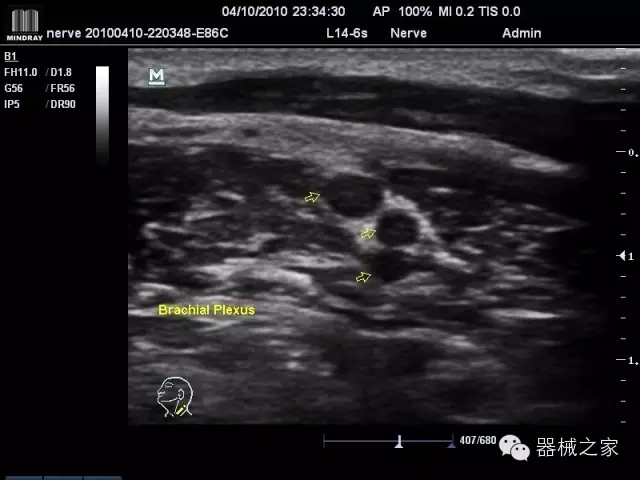

臨床圖片賞析

·優(yōu)秀的圖像效果、強(qiáng)大的功能體驗(yàn)、豐富的探頭選擇、合理的便攜式設(shè)計,全中文顯示及病人管理界面,使得M7在任何場合、任何時候都能快速響應(yīng)更好的心血管、腹部、婦產(chǎn)、小器官等常規(guī)超聲檢查以及肌骨、神經(jīng)、顱腦、術(shù)中等新興領(lǐng)域的使用需求;